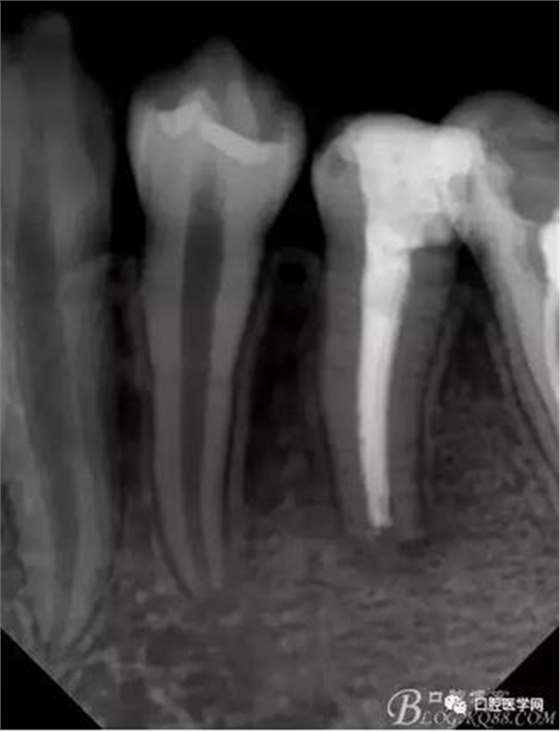

去除暫封,生理鹽水沖洗,發(fā)現(xiàn)已經(jīng)形成根尖封閉,15#根管挫也無法通過根尖孔,忘記拍一張X片了。然后行根管充填。

因門診條件不足,沒有橡皮障,沒有口內(nèi)圖片,也沒有 ProTaper鎳鈦器械,更沒有機(jī)擴(kuò)。不然就更加完美了。